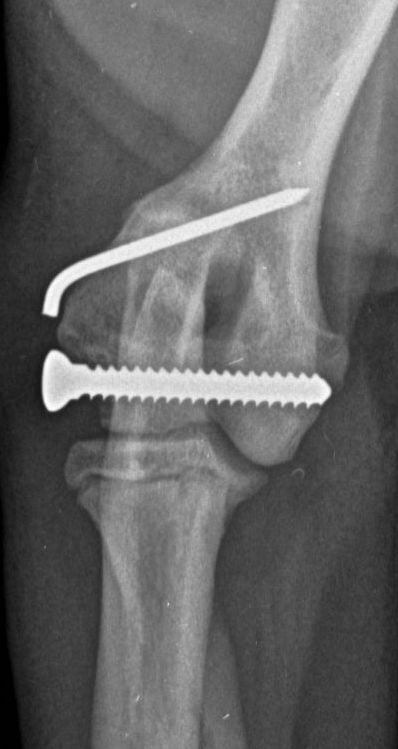

These concerns have led to recommendations being altered over the past decade or so, with veterinarians now using bone plates, instead of K-wires, as an adjunct to a transcondylar screw when managing humeral unicondylar fractures (Figure 2), even in puppies (Figure 3) (Clark, 2016; Kvale et al., 2022). However, the basis on which this conclusion for puppies was reached appears to have been flawed because it assumed that what had been shown to be the case for adults would also apply to immature patients. As the conclusion was felt to conflict with the author’s experience of treating such patients, a retrospective study was undertaken to evaluate complications and outcomes in immature dogs treated for humeral unicondylar fractures at one centre over a 10-year period (Butterworth, 2022). The findings of this study are summarised in this article.